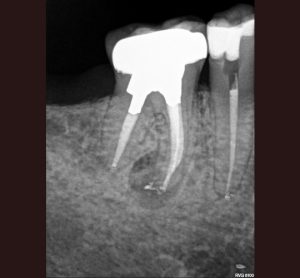

AllAccess Design and ClosureApexificationCBCT DiagnosisCracked TeethCrown Build-upEndodontic MicrosurgeryEndodontic RetreatmentEndodonticsImplantsInternal BleachingMB RootResorption Repair Endodontic Treatment: Case #1- Patient referred due to pain after recent crown cementation. Endodontic Treatment: Case #2 -Patient referred due to pain in her upper first pre molar tooth # 4 Endodontic Treatment: Case #3 – Patient referred due to pain to biting. The amalgam filling was done many years ago. Endodontic Treatment: Case #4 – Patient presented for root canal therapy referred to our office due to complex root anatomy. Endodontic Treatment: Case #5 – Necrotic (dead nerve) tooth with biting pain. Endodontic Treatment: Case #6- Necrotic (dead nerve) tooth with no pain referred for treatment. Endodontic Treatment: Case #7- Very unique tooth with lots of canals (this was a dentists tooth!) Endodontic Treatment: Case #8 – recently prepared for a crown. The patient has cold sensitivity and was referred for treatment. Endodontic Treatment: Case #9- Interesting root anatomy and diagnosis. Endodontic Treatment: Case #10 – 4 canalled lower first molar with 2 distals and 2 mesial canals with a common apex of the mesial root system. Endodontic Treatment: Case #11 Endodontic Treatment: Case #12- Four canalled lower first molar. Finding MB2 The MB Root: Case # 1 The MB Root: Case #2 The MB Root: Case #3 The MB Root: Case #4 The MB Root: Case #5 The MB Root: Case #6 The MB Root: Case #7 The MB Root: Case #8 The MB Root: Case #9 Maxillary MB Root: 1 Mandibular MB Root: 1 Mandibular MB Root: 2 Maxillary MB Root: 2 Mandibular MB Root: 3 Maxillary MB Root: 3 Mandibular MB Root: 4 Endodontic Retreatment: Case #1 – Silver point root canal that was performed 30 years earlier. Endodontic Retreatment: Case #2- Retreatment of initial root canal done 15 years earlier. Endodontic Retreatment: Case #3- Retreatment of a recent root canal performed 2 weeks earlier. Endodontic Retreatment: Case #4 – Retreatment of initial root canal done 12 years earlier Endodontic Retreatment: Case #5 – Retreatment of initial root canal done 30 years earlier. Endodontic Microsurgery: Case #1 Endodontic Microsurgery: Case #2 Endodontic Microsurgery: Case #3 Endodontic Microsurgery: Case #4 Endodontic Microsurgery: Case #5 – Intentional replantation (not so common procedure) Access Closure: Case #1 Access Closure: Case #2 Access Closure: Case #3 Access Closure: Case #4 Access Closure: Case #5 Access Closure: Case #6 Access Closure: Case #7 Access Closure: Case #8 Access Closure: Case #9 Access Closure: Case #10 Access Closure: Case #11 Crown Build-up: Case #1 Crown Build-up: Case #2 Crown Build-up: Case #3 – with bicuspid teeth they are more prone to fracture. Crown Build-up: Case #4 – with bicuspid teeth they are more prone to fracture. Crown Build-up: Case #5 Crown Build-up Case #6 Cracked Teeth: Case #1 Cracked Teeth: Case #2 Cracked Teeth: Case #3 Cracked Teeth: Case #4 Cracked Teeth: Case #5 Cracked Teeth: Case #6 Cracked Teeth: Case #7 Implants: Case #2 Implants: Case #3 Implants: Case #1 Implants: Case #10 Implants: Case #9 Implants: Case #8 Implants: Case #7 Implants: Case #6 Implants: Case #5 Implants: Case #4 CBCT Diagnosis: Case #12 CBCT Diagnosis: Case #11 CBCT Diagnosis: Case #10 CBCT Diagnosis: Case #9 CBCT Diagnosis: Case #8 CBCT Diagnosis: Case #7 CBCT Diagnosis: Case #6 CBCT Diagnosis: Case #5 CBCT Diagnosis: Case #4 CBCT Diagnosis: Case #3 CBCT Diagnosis: Case #2 CBCT Diagnosis: Case #1 High Magnification of Resorption Resorption Repair: Case #5 Resorption Repair: Case #4 Resorption Repair: Case #3 Resorption Repair: Case #2 Resorption Repair: Case #1 Internal Bleaching: Case #3 Internal Bleaching: Case #2 Internal Bleaching: Case #1 Apexification of Lower Premolar